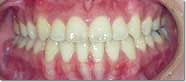

●主 訴 ― 叢生

●治療期間 ― 約3ヶ月

●治療内容 ― FLB舌側矯正装置、及びヘミオステオトミーによるスピード矯正(非抜歯ケース) |